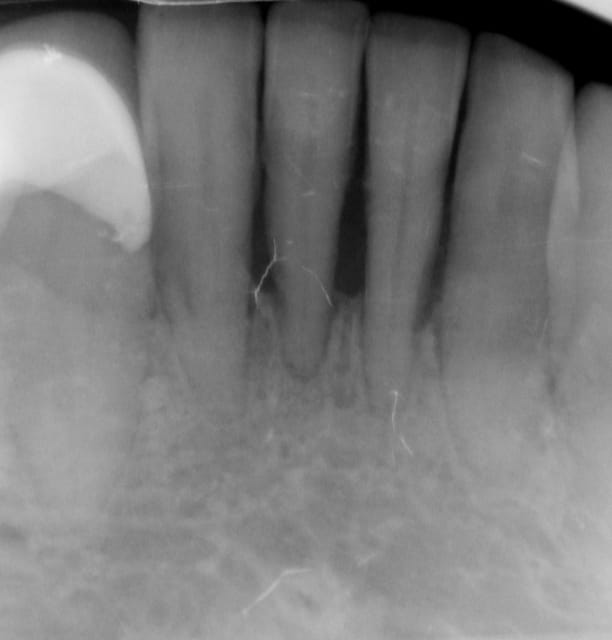

> feriez-vous le même traitement a un patient de 30 ans???

> problèmes de distance inter-implants

Pour un patient de 30 ans, pourquoi pas.Mais on peut implanter seulement 6 à 8 pour une prothèse fixée.Et 4 implants pour une prothèse amovible dans la mandibula.

Pour la distance inter-implants c est une bonne remarque, le distance réglementaire est de 2/3mm en méthode conventionelle , ici c´est une variante du flapless en forant de manière à condenser l´os via un foret à 3 faces. En préservant le périoste on a remarqué que cette distance réglementaire pouvait être plus petite. C est une observation , qui marche (en flaples) dans ma pratique et dans celles de mes confrères Allemands, à ma connaissance pas enormément documenté . Ceci dit il y a un livre en francais qui en parle "implantologie flapless" de Byung Ho Choi et wilfried Engelke (Pr de Göttingen).

Sur le cas posté au début la dernière radio est après deux ans post OP. Ci dessous un autre exemple.

Les 12 premières photos sont un même cas avec implantation immédiate.

Le deuxième cas c est les photos 13 14 15 , (la photo 14 et 15 est après 5 ans)

Le dernier cas (3 dernieres photos), a été realisé il y a 5 ans il n y a pas de problème, je ne trouve pas les radios malheureusement je vais chercher encore un peu dans la journée.